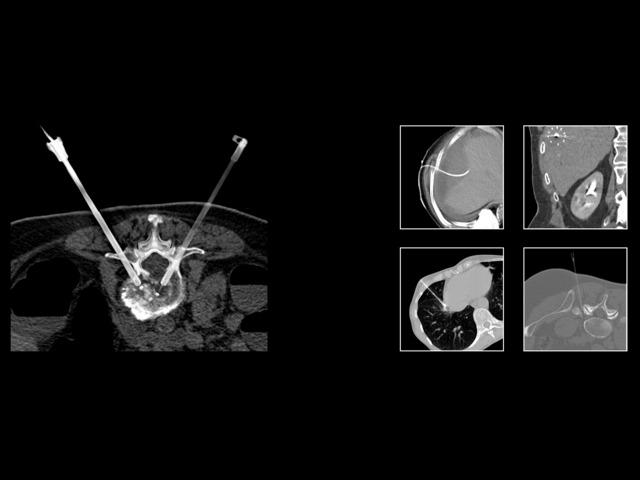

Advanced laser guidance to improve CT-guided interventionsSee how Iowa Methodist is doing it